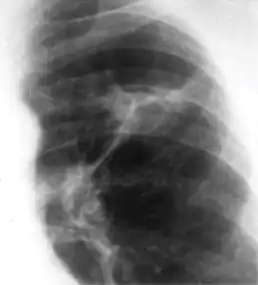

In countries where cow milk infected with Mycobacterium bovis has been eliminated (due to culling of infected cows and pasteurization), primary tuberculosis is usually caused by Mycobacterium tuberculosis and almost always begins in the lungs. Typically, the inhaled bacilli implant in the distal airspaces of the lower part of the upper lobe or the upper part of the lower lobe, usually close to the pleura. As sensitization develops, a 1 to 1.5 cm area of gray-white inflammation with consolidation emerges, known as the Ghon focus. In most cases, the center of this focus undergoes caseous necrosis. Tubercle bacilli, either free or within phagocytes, drain to the regional nodes, which also often caseate. This combination of parenchymal lung lesion and nodal involvement is referred to as the Ghon complex. During the first few weeks, there is also lymphatic and hematogenous dissemination to other parts of the body.

The Ghon complex undergoes progressive fibrosis, often followed by radiologically detectable calcification (Ranke complex), and despite seeding of other organs, no lesions develop. Although they are often confused, Ranke complex and Ghon complex are not synonymous. The Ranke complex is an evolution of the Ghon complex (resulting from further healing and calcification of the lesion).[4][5]